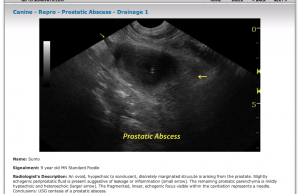

The image shown is from the Atlas of Veterinary Sonographic Pathology. It shows the biopsy needle coming straight down into the prostate. How was that done- from the side of the probe?

From the angle of the needle is seems that the needle was introduced from the side of the probe.